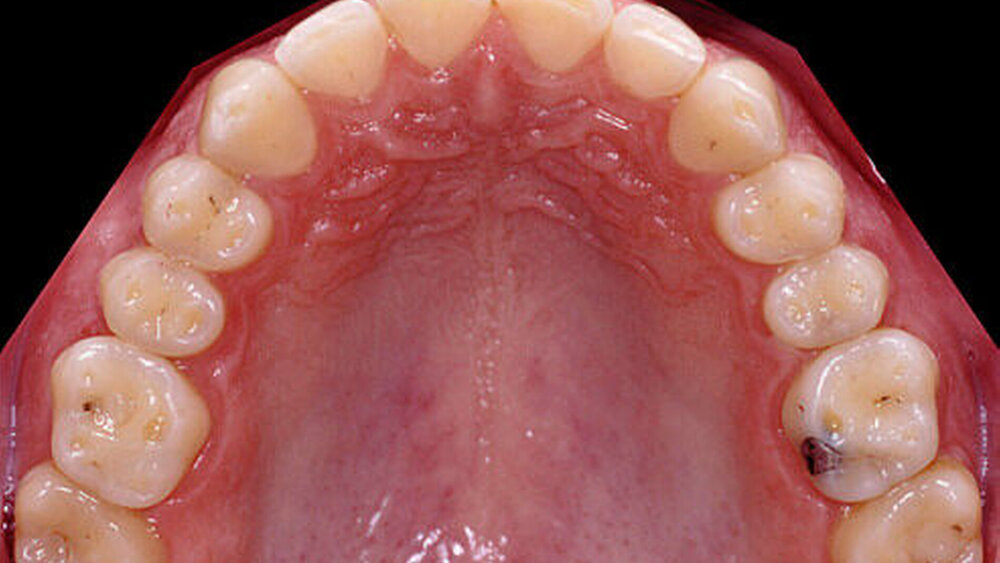

Nach einer klinischen Funktionsanalyse (Abbildungen 1 und 2) werden Situationsmodelle hergestellt und diese anhand einer arbiträren Scharnierachsbestimmung und eines Zentrikregistrats im Artikulator montiert. Die für die spätere Versorgung funktionell und ästhetisch ideale Vertikaldimension wird durch ein analytisches Wax-up eingestellt (Abbildung 3). Dieses wird in eine diagnostische Schablone (Tiefziehfolie) für eine „ästhetische Evaluierung“ durch den Zahnarzt und den Patienten überführt. Dazu kann die Schablone mit niedrigviskösem Komposit gefüllt und reversibel auf die mit flüssiger Vaseline isolierten Zähne gesetzt werden. Findet dieser Restaurationsvorschlag die Zustimmung des Patienten, wird im zahntechnischen Labor eine in der Höhe und in der Bisslage dem Wax-up entsprechende Repositionsschiene mit Front-Eckzahn-Führung angefertigt. Diese Schiene sollte circa drei Monate möglichst permanent getragen werden. Diese „funktionelle Evaluierung“ dient dazu zu prüfen, ob der Patient die neue Bisslage beschwerdefrei toleriert [Edelhoff et al., 2013; Harper, 2000; Rivera-Morales et al.,1992].